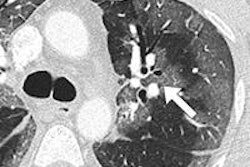

A new study out of Saudi Arabia is giving radiologists a better look at the presentation of Middle East respiratory syndrome (MERS) on CT.

Until now, radiologists had to make do with clinical studies of MERS in nonradiology journals, which lacked the specificity that imaging professionals might want to make an accurate diagnosis. But a new paper in the American Journal of Roentgenology describes the pathology in a language radiologists can understand.